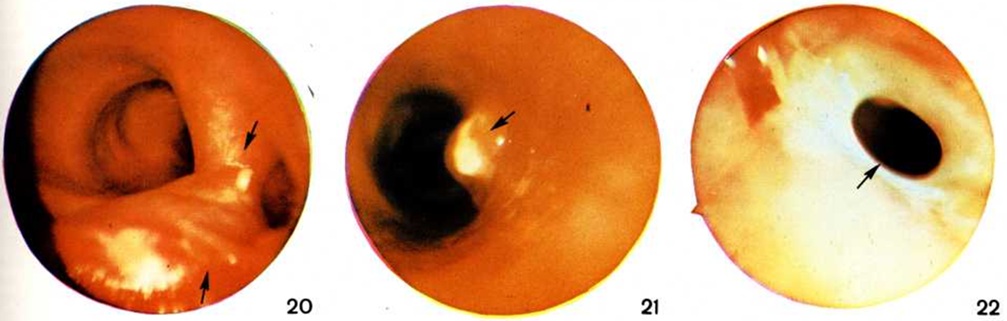

Рис. 8.

Рентгенограмма грудной клетки при инфильтративном туберкулёзе лёгких (прямая проекция): стрелкой указан инфильтрат округлой формы.

Рис. 9.

Томограмма правого лёгкого при инфильтративном туберкулёзе лёгких (боковая проекция): стрелкой указан инфильтрат в лёгочной ткани с полостью распада.

Рис. 10.

Рентгенограмма грудной клетки при инфильтративном туберкулёзе лёгких (прямая проекция): стрелкой указан инфильтрат в верхней доле правого лёгкого (лобит) с полостью распада.